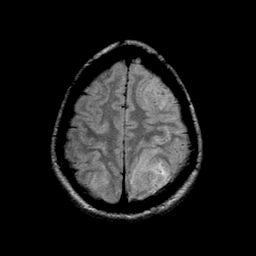

Sarcoma, MR Study #1 mr-pd -- Slice #20

[Home][Help][Clinical] Slice 20